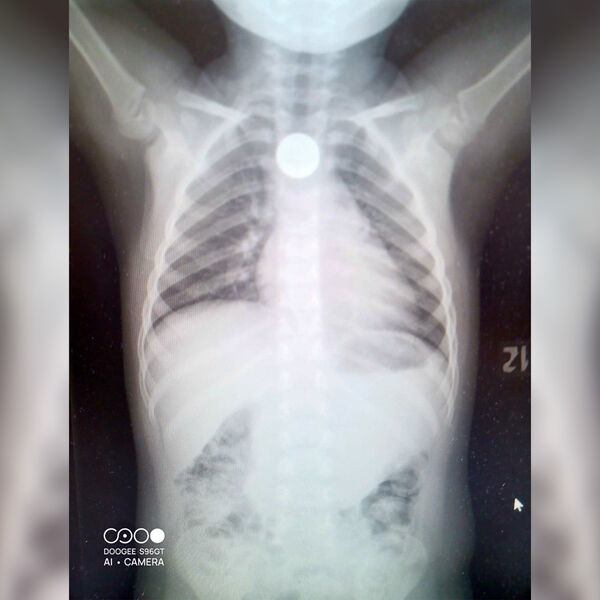

Хирурги осмотрели мальчика и приняли решение срочно направить его на рентген. В пищеводе ребенка обнаружили инородное тело — это была монета, которая застряла в одном из физиологических сужений.

Мальчика доставили в кабинет эндоскопии. Врачи экстренно удалили инородное тело из пищевода ребенка — это оказалась монета номиналом в один рубль.